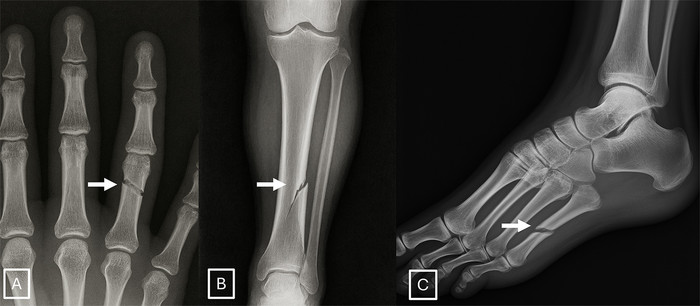

| ▲ GPT-4o로 생성된 골절 방사선 사진의 예: (A) 손의 후전방 방사선 사진, (B) 하퇴의 후전방 방사선 사진, (C) 발의 내측 사선 방사선 사진. 이미지에서 골절선(화살표)은 비정상적으로 매끄럽고 깨끗하며 일관성을 보이고, (B)의 경우 단일 피질 골절입니다. 이러한 비정상적인 매끄러움과 불완전한 피질 파괴를 특징으로 하는 이상적인 골절선의 존재는 인공지능으로 생성된 외상 이미지를 식별하는 주요 진단 단서로 활용될 수 있다. (출처:Mar 24 2026 / The Rise of Deepfake Medical Imaging: Radiologists’ Diagnostic Accuracy in Detecting ChatGPT-generated Radiographs / Radiology) |

이번 실험을 통해 AI가 생성한 엑스레이 이미지를 식별하는 방법에 대한 단서도 얻을 수 있었다. 토르드즈만 연구원은 "딥페이크 이미지는 지나치게 완벽해 보이는 경우가 많다"며, "뼈가 지나치게 매끄럽고, 척추가 비정상적으로 곧으며, 폐가 지나치게 대칭적이다"고 그는 설명했다. 가짜 엑스레이에서 골절 부위 또한 비정상적으로 깨끗하고 균일하게 나타나며, 뼈의 한쪽 면에만 국한되는 경우가 흔하다.